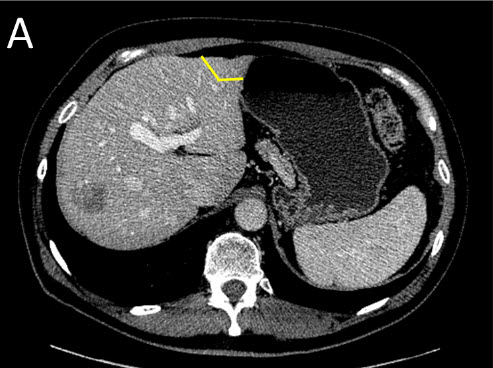

![]() |

(A) Staged Liver Resection: First Surgery (Stage I) - the tumors on the future remnant liver are treated first by resection or ablation |